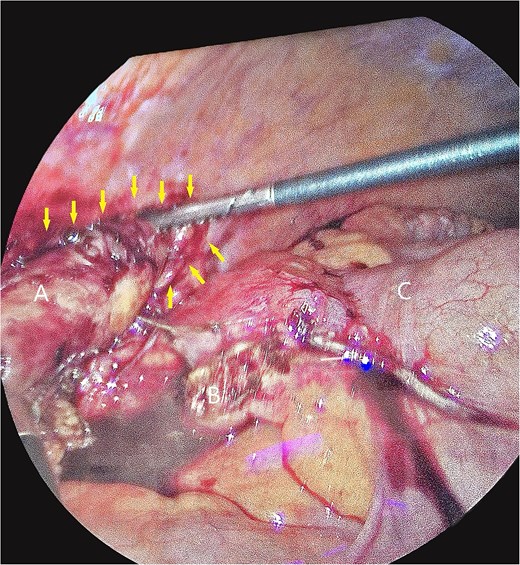

Axial images of CT scan with IV contrast showing appendix within retrocecal position in proximity within iliacus space. (A) Appendix; (B) iliacus muscle; (C) cecum.

The patient underwent laparoscopic appendectomy with laparoscopic enterolysis. The appendix appeared inflamed, dilated, and gangrenous, with a perforation located 2 cm from the base. Notably, the appendix was not in a retrocecal position as initially suspected but was found to be herniating through a defect in the iliacus muscle (Fig. 3). The appendix was circumferentially freed from the hernia defect, which was identified as tracking cephalad between the iliacus muscle and the iliac bone. The hernia defect measured 2.5 cm and was primarily closed using two figure-of-eight 2–0 Vicryl sutures, leaving a small inferior opening to allow for drainage (Fig. 4). A 19 Fr Blake drain was placed in the right lower quadrant and paracolic gutter.

Intra-operative photos of appendix contained within iliacus hernia after appendix was divided. The arrows showcase the hernia with appendix. (A) Appendix, (B) mesoappendix after division, (C) cecum with staple line.